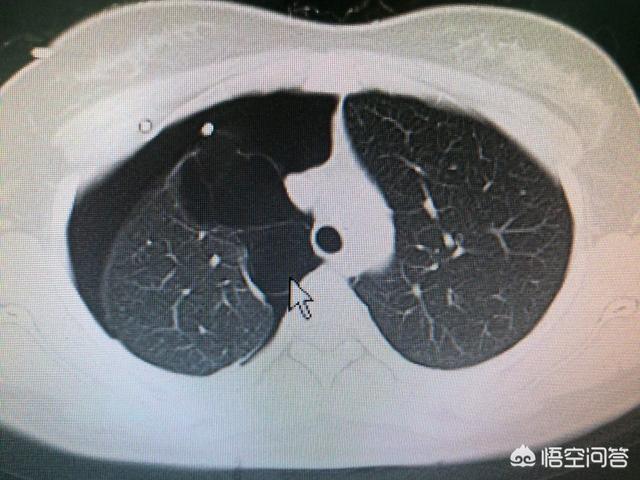

2.肺のCT検査。肺CT検査では、肺の肺気腫だけでなく慢性気管支炎の重症度も観察できるため、間接的に患者の重症度を判断することができる。

気胸が疑われる場合、主な検査は画像診断である。胸部X線と胸部CT.通常、気胸の存在を確認するには胸部X線検査で十分であり、患者によっては胸部CT検査が行われることもある。

胸のつかえや息切れに咳の症状が伴う場合は、なおさら呼吸器疾患を疑う必要があります。 肺や気管の病気をまず除外し、呼吸器内科で医師の指示を仰ぐようにしましょう。胸部レントゲン写真や胸部CTでさらに診断を明確にします。